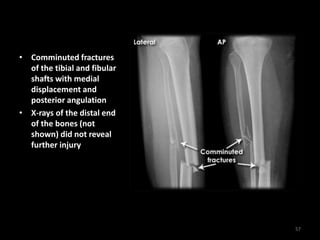

Tibial and fibular fracture

56

• Comminuted fractures

of the tibial and fibular

shafts with medial

displacement and

posterior angulation

• X-rays of the distal end

of the bones (not

shown) did not reveal

further injury

57